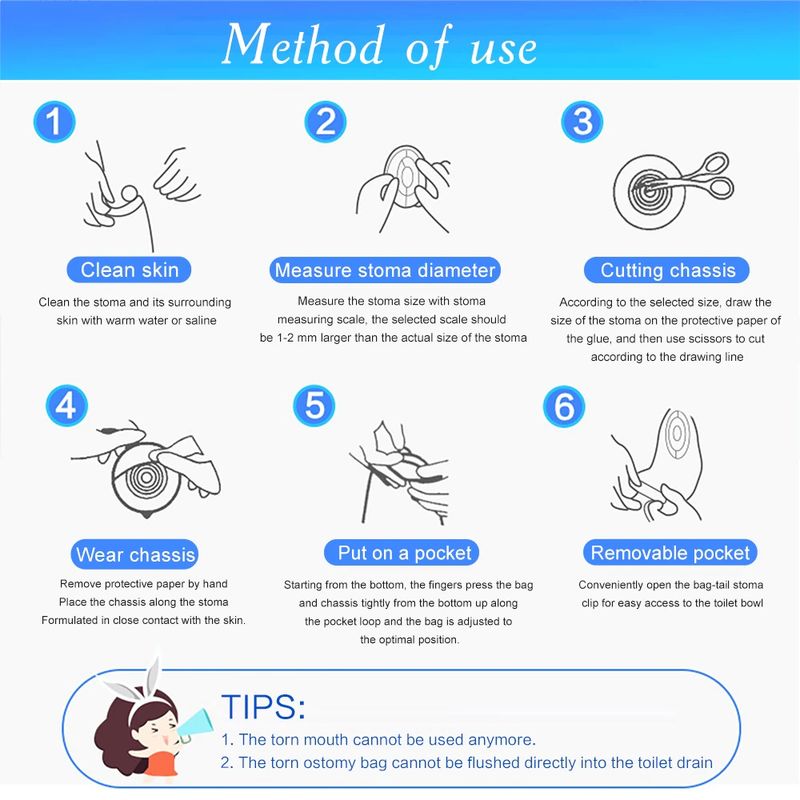

Descripción del producto La bolsa de cuidado de ostomía combina la barrera de la piel y la bolsa de colección en un sistema simple y fácil de administrar, proporcionando una gran simplicidad. La bolsa de colostomía es fácil de aplicar con el cierre de Velcro adjunto, proporcionando seguridad, ya que los sujetadores de plástico se bloquean en su lugar, fáciles de vaciar y irrigar. El propósito de reemplazar la ostomía 1. Observa la mucosa del estoma, las suturas circundantes y la piel circundante. 2. Limpia la piel alrededor del estoma, reduce el olor y aumenta la comodidad. 3. Evita que el agua fecal contamine la incisión abdominal a través de la fuga del chasis. 4. Si hay impregnación, asegúrese de reemplazarla a tiempo. Se recomienda cambiar el tiempo de 3-5 días para garantizar una respiración efectiva de la piel. Sentido común de la vida ostomía 1. Comer uniformemente, beber mucha agua y comer más verduras y frutas. 2. Evite comer demasiado rápido y tragar aire, masticar alimentos lentamente, Evite hablar mientras come, evite comer demasiado de una vez. 3. Evite las comidas con alto contenido de fibra y evite el bloqueo del estoma. 4. La ropa es suave y cómoda. 5. Evita el trabajo para aumentar la presión abdominal (como extraer objetos pesados). 6. Mantenga su estado de ánimo feliz. Paquete 10 unids/caja bolsa de ostomía